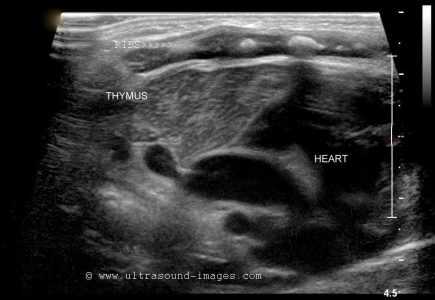

Фото. Объемное образование в средостение у мальчика 14-ти лет, который завершил курс химиотерапии по поводу первичной медиастинальной Т-клеточной лимфомы 6 месяцев назад. Направляющий диагноз: рецидив лимфомы. На поперечном срезе УЗИ: нормальный тимус (стрелки) с ровными и четким контуром, менее эхогенный чем щитовидная железа. AA — дуга аорты, PA — легочная артерия.

У больных с раком важная диагностическая задача отличить гиперплазию тимуса от метастазов. Гиперплазия тимуса на УЗИ: равномерное увеличение, ровный и четкий контур, не тронутые окружающие сосуды, диффузная неоднородность эхо-структуры за счет гиперэхогенного жира и гипоэхогенной лимфоидной ткани. Опухоли в тимусе, как правило, округлые, с неровным контуром, часто содержат очаги некроза или обызвествления.

Важно. Тимус очень пластичный и не вызывает сжатие или смещение соседних структур, поэтому сердечные пульсации и дыхательные движения влияют на форму тимуса. В отличие от этого, солидные опухоли или диффузной инфильтрационной процессы менее податливым и более жесткими.

На УЗИ тимус гипоэхогенный в сравнении с щитовидной железой, и изоэхогенный миакарду. Контур тимуса четкий; ровный по передней поверхности, но волнистый сзади. У детей младшего возраста эхо-структура железы однородная мелкозернистая, а у старших детей и взрослых точечные гипо- и гиперэхогенные сигналы перемежают — это смесь жира и лимфоидной ткани. Внутри тимуса можно разглядеть тонкие гиперэхогенные фиброзные перегородки, которые делят железу на отсеки. Из-за фиброзной капсулы края тимуса хорошо контурируют. Расположение, форма и размер тимуса сильно варьируют.